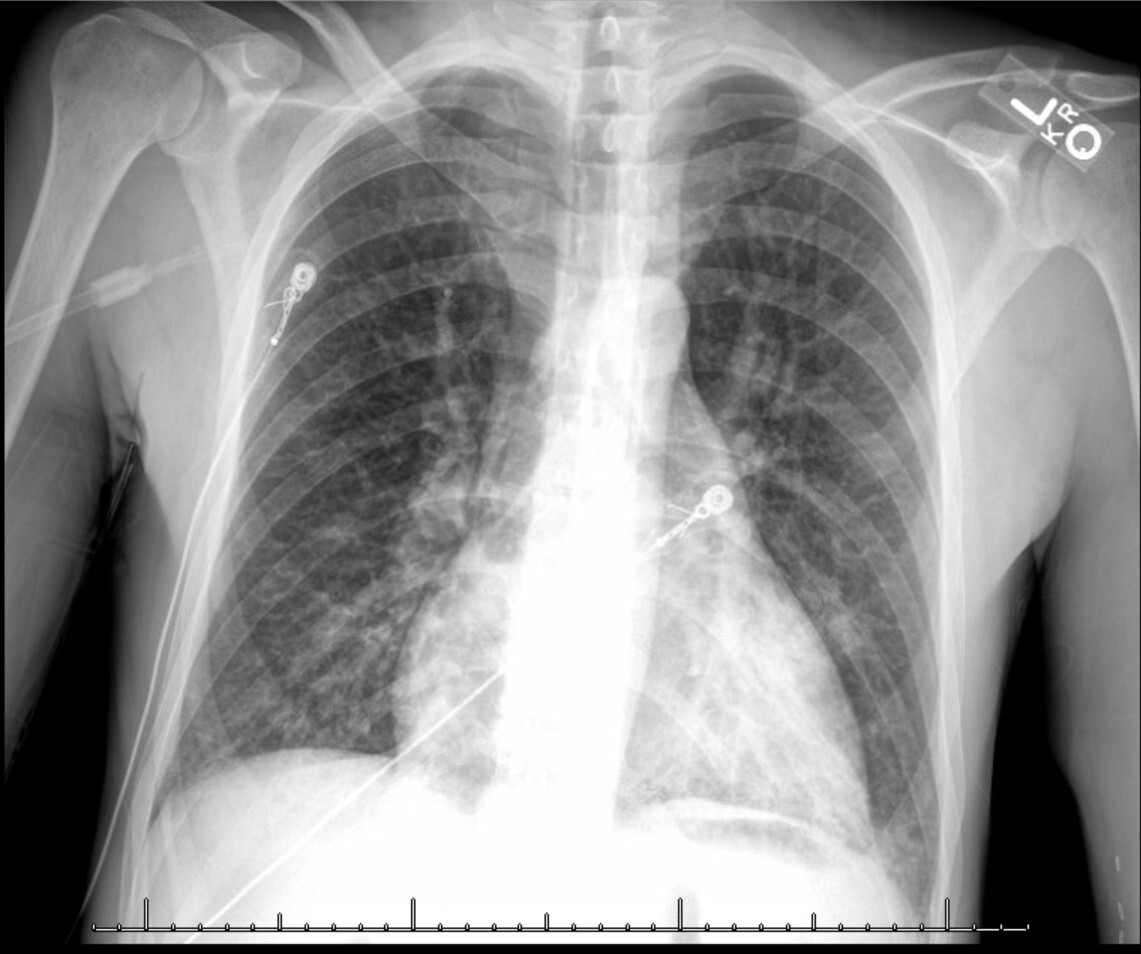

The patient is a 32-year-old male with a history of end-stage renal disease on hemodialysis secondary to a distant history of poststreptococcal glomerulonephritis who presented to the emergency department due to hemoptysis. He reported that two weeks prior he had a similar episode but it self-resolved. He had no fevers or sick contacts. Family history revealed that he had a sibling who recently expired from pulmonary complications of dermatomyositis. The patient was in clear distress from persistent hemoptysis with evidence for upper airway edema including stridor and hoarseness. He experienced brief syncope twice. Due to his presentation and concerns of instability we discussed intubation with our patient and he expressed hesitancy and became emotional due to his sibling’s recent passing following intubation. Alternative measures for stabilization were considered and nebulized tranexamic acid was administered. This resulted in swift improvement of coughing episodes and resolution of hemoptysis. The intensive care unit was consulted, and the patient was admitted in stable condition. There was no relapse of hemoptysis during his hospital course. During admission, the patient was electively intubated for bronchoscopy with cryotherapy for clot removal from the upper and lower airways. Chest radiography demonstrated interstitial opacities of the lung bases bilaterally (Figure 1). Chest computed tomography angiography confirmed left lower lobe pneumonia with cavitating pulmonary nodules, without evidence of pulmonary embolism (Figure 2). Autoimmune workup was significant only for myeloperoxidase antibodies. Respiratory culture was positive for P. aeruginosa and Methicillin-sensitive S. aureus. The patient was diagnosed with hemorrhagic pneumonia, treated with broad spectrum antibiotics, and discharged with follow-up for further outpatient workup.